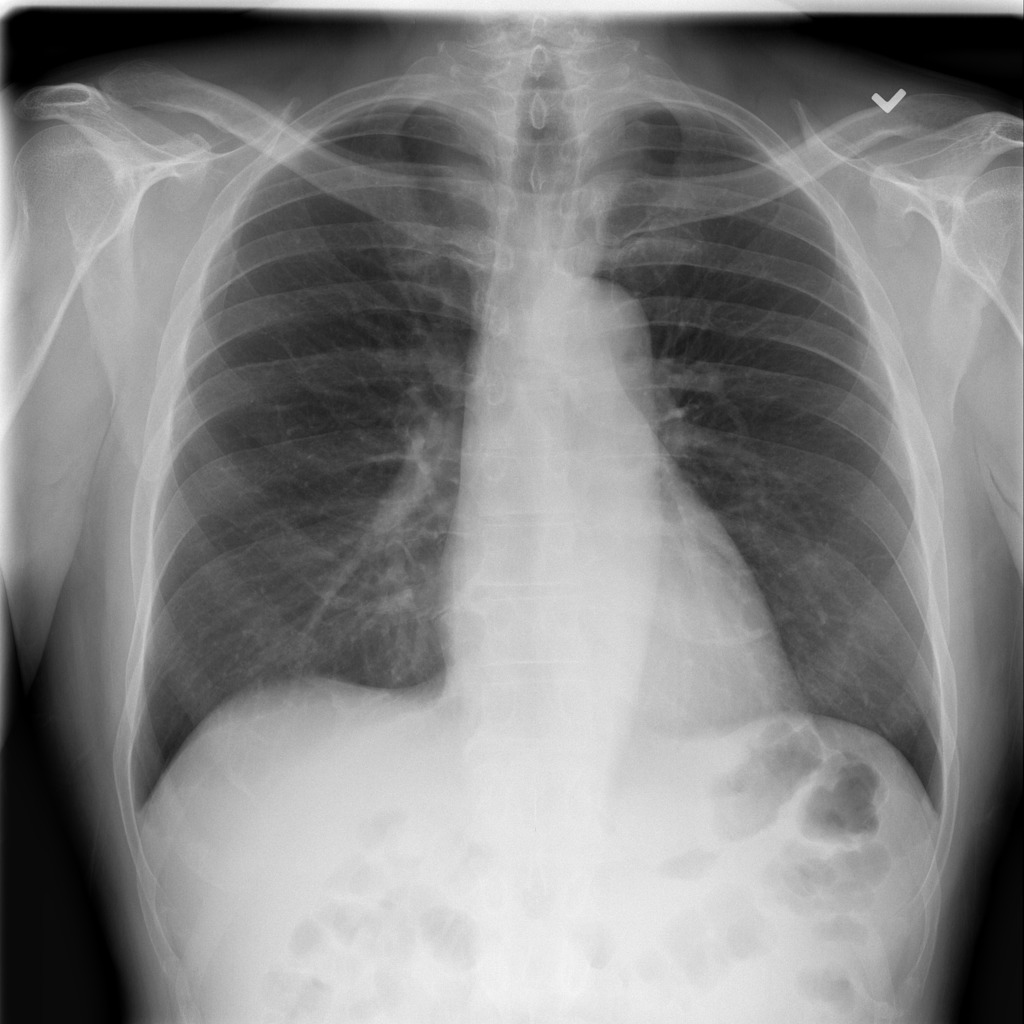

In this sub-section, we concisely inaugurate the benchmark data set, named COVIDx[22], that used in our experiment. To the best of our knowledge, this data set is one of the largest open-access benchmark data set for the number of COVID-19 infection cases, and the total number of 14,914 images for training and 1,579 images for testing, comprising three categories of COVID-19, normal and pneumonia333Access on July 17, 2020. Figure 1 shows sample images from the benchmark dataset, including COVID-19, normal and pneumonia. Table 2 depicts the distribution of images in training and testing sets. To generate the COVIDx, the authors[22] used five different publicly accessible data repositories:

Refer to caption

(a) COVID-19

(b) Normal

(c) Pneumonia

Figure 1: Some image labels available in the benchmark dataset [22]